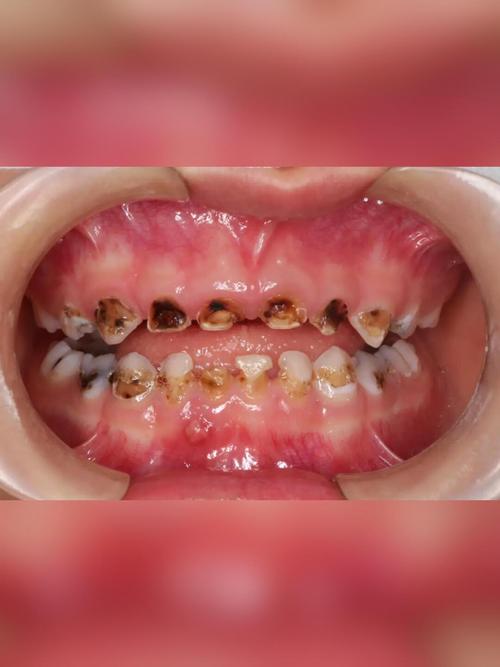

生活习惯和饮食因素对门牙蛀牙的影响也不容忽视,现代饮食中,高糖食物和酸性饮料的摄入量增加,如碳酸饮料、果汁、糖果、糕点等,这些食物不仅含有大量糖分,其酸性也会直接腐蚀牙釉质,门牙作为切割食物的主要牙齿,在进食时首先接触这些食物,更容易受到直接攻击,频繁饮用碳酸饮料而不及时漱口或清洁,会导致牙釉质表面被酸蚀,变得粗糙,更容易附着细菌和食物残渣,不良的口腔卫生习惯,如刷牙次数不足、刷牙方法不正确(如未采用巴氏刷牙法,遗漏牙面)、不使用牙线清洁邻面等,都会导致牙菌斑和牙结石堆积,为细菌提供了繁殖的温床,对于儿童来说,门牙蛀牙还可能与“奶瓶龋”有关,即长时间含着奶瓶或母乳入睡,牛奶中的乳糖在口腔中被细菌分解,产生酸性物质,腐蚀门牙。

问:儿童门牙蛀牙(奶瓶龋)需要治疗吗?

答:儿童门牙蛀牙(奶瓶龋)必须及时治疗,乳牙虽然会被恒牙替换,但乳牙的健康对恒牙的发育、颌骨的生长以及儿童的咀嚼、发音和心理发育都有重要影响,奶瓶龋进展迅速,容易导致乳牙牙冠大面积破坏,引发疼痛、感染,甚至影响下方恒牙胚的发育,治疗方法包括涂氟、补牙、根管治疗等,具体需根据龋坏程度由医生决定,家长应注意纠正儿童含奶瓶入睡的习惯,饭后漱口,并尽早开始口腔清洁,帮助儿童养成良好的口腔卫生习惯。